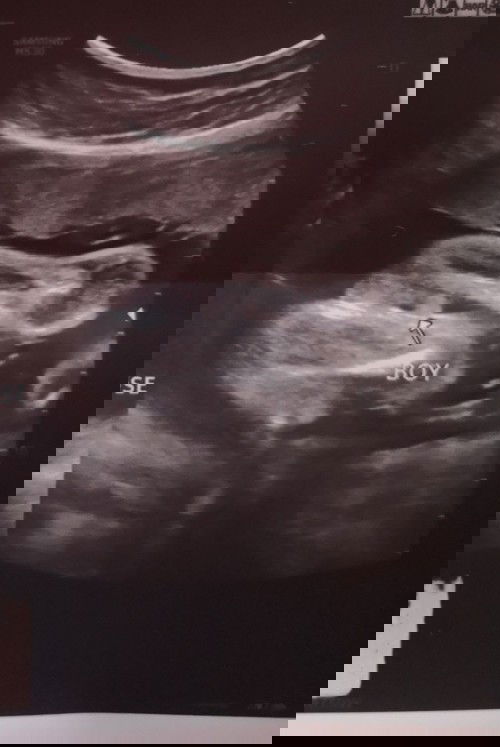

Confirm po ba na Boy po yung baby ko? Sa tingin nyo po hehe first time Mom po ako. Thank you po sa mga sasagot.#1stimemom #pregnancy

Yes, mommy. Ganyan din sa LO ko. :) Pag girl kasi three lines, may hiwa and hambuger sign.